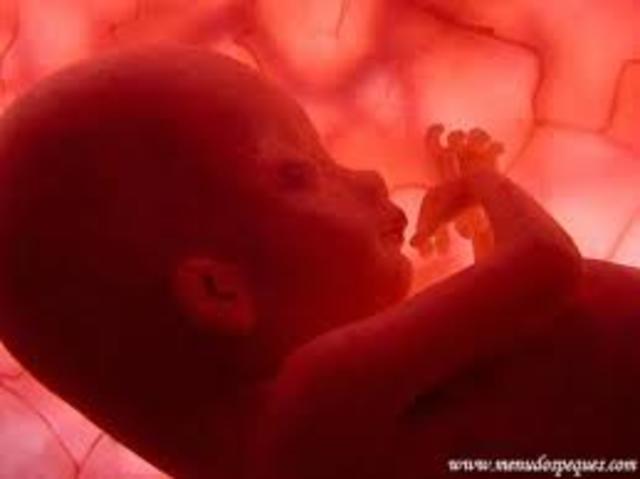

• (Feto 12 semanas):

(Feto 12 semanas):

En la semana 9 ., el peso del feto es de 8gr y al momento de nacer alcanza un peso aproximado de 3000gr

En el mismo lapso ., su longitud aumenta de 5cm a 50 cm ., en las semanas fetales la cabeza sigue siendo muy grande ., mientras que el tronco va aumentando poco a poco de tamaño